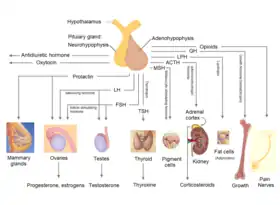

Hormones secreted from the pituitary gland help to control growth, blood pressure, energy management, all functions of the sex organs, thyroid glands, metabolism, as well as some aspects of pregnancy, childbirth, breastfeeding, water/salt concentration at the kidneys, temperature regulation, and pain relief.

Functions

The anterior pituitary regulates several physiological processes by secreting hormones. This includes stress (by secreting ACTH), growth (by secreting GH), reproduction (by secreting FSH and LH), metabolism rate (by secreting TSH) and lactation (by secreting prolactin). The intermediate lobe synthesizes and secretes melanocyte-stimulating hormone. The posterior pituitary (or neurohypophysis) is a lobe of the gland that is functionally connected to the hypothalamus by the median eminence via a small tube called the pituitary stalk (also called the infundibular stalk or the infundibulum). It regulates hydroelectrolytic stability (by secreting ADH), uterine contraction during labor and human attachment (by secreting oxytocin).

The anterior pituitary synthesizes and secretes hormones. All releasing hormones (-RH) referred to can also be referred to as releasing factors (-RF).

- Human growth hormone (HGH), also referred to as 'growth hormone' (GH) or somatotropin, is released under the influence of hypothalamic growth hormone-releasing hormone (GHRH), and is inhibited by hypothalamic somatostatin.

- Cleaved from the precursor proopiomelanocortin protein, and include adrenocorticotropic hormone (ACTH), and beta-endorphin, and melanocyte-stimulating hormone are released under the influence of hypothalamic corticotropin-releasing hormone (CRH).[9][10]: 1210

- Thyroid-stimulating hormone (TSH) is released under the influence of hypothalamic thyrotropin-releasing hormone (TRH) and is inhibited by somatostatin.

- Luteinizing hormone (LH).

- Follicle-stimulating hormone (FSH), both released under influence of Gonadotropin-releasing Hormone (GnRH)

- Prolactin (PRL), whose release is inconsistently stimulated by hypothalamic TRH, oxytocin, vasopressin, vasoactive intestinal peptide, angiotensin II, neuropeptide Y, galanin, substance P, bombesin-like peptides (gastrin-releasing peptide, neuromedin B and C), and neurotensin, and inhibited by hypothalamic dopamine.[11]

These hormones are released from the anterior pituitary under the influence of the hypothalamus. Hypothalamic hormones are secreted to the anterior lobe by way of a special capillary system, called the hypothalamic-hypophysial portal system.

The intermediate lobe synthesizes and secretes the following important endocrine hormone:

- Melanocyte–stimulating hormone (MSH). This is also produced in the anterior lobe.[12] When produced in the intermediate lobe, MSHs are sometimes called "intermedins".

The posterior pituitary stores and secretes (but does not synthesize) the following important endocrine hormones:

- Antidiuretic hormone (ADH, also known as vasopressin and arginine vasopressin AVP), the majority of which is released from the supraoptic nucleus in the hypothalamus.

- Oxytocin, most of which is released from the paraventricular nucleus in the hypothalamus. Oxytocin is one of the few hormones to create a positive feedback loop. For example, uterine contractions stimulate the release of oxytocin from the posterior pituitary, which, in turn, increases uterine contractions. This positive feedback loop continues throughout labour.

Hormones secreted from the pituitary gland help control the following body processes:

- Growth (GH)

- Blood pressure

- Some aspects of pregnancy and childbirth including stimulation of uterine contractions

- Breast milk production

- Sex organ functions in both sexes

- Thyroid gland function

- Metabolic conversion of food into energy

- Water and osmolarity regulation in the body

- Water balance via the control of reabsorption of water by the kidneys

- Temperature regulation

- Pain relief